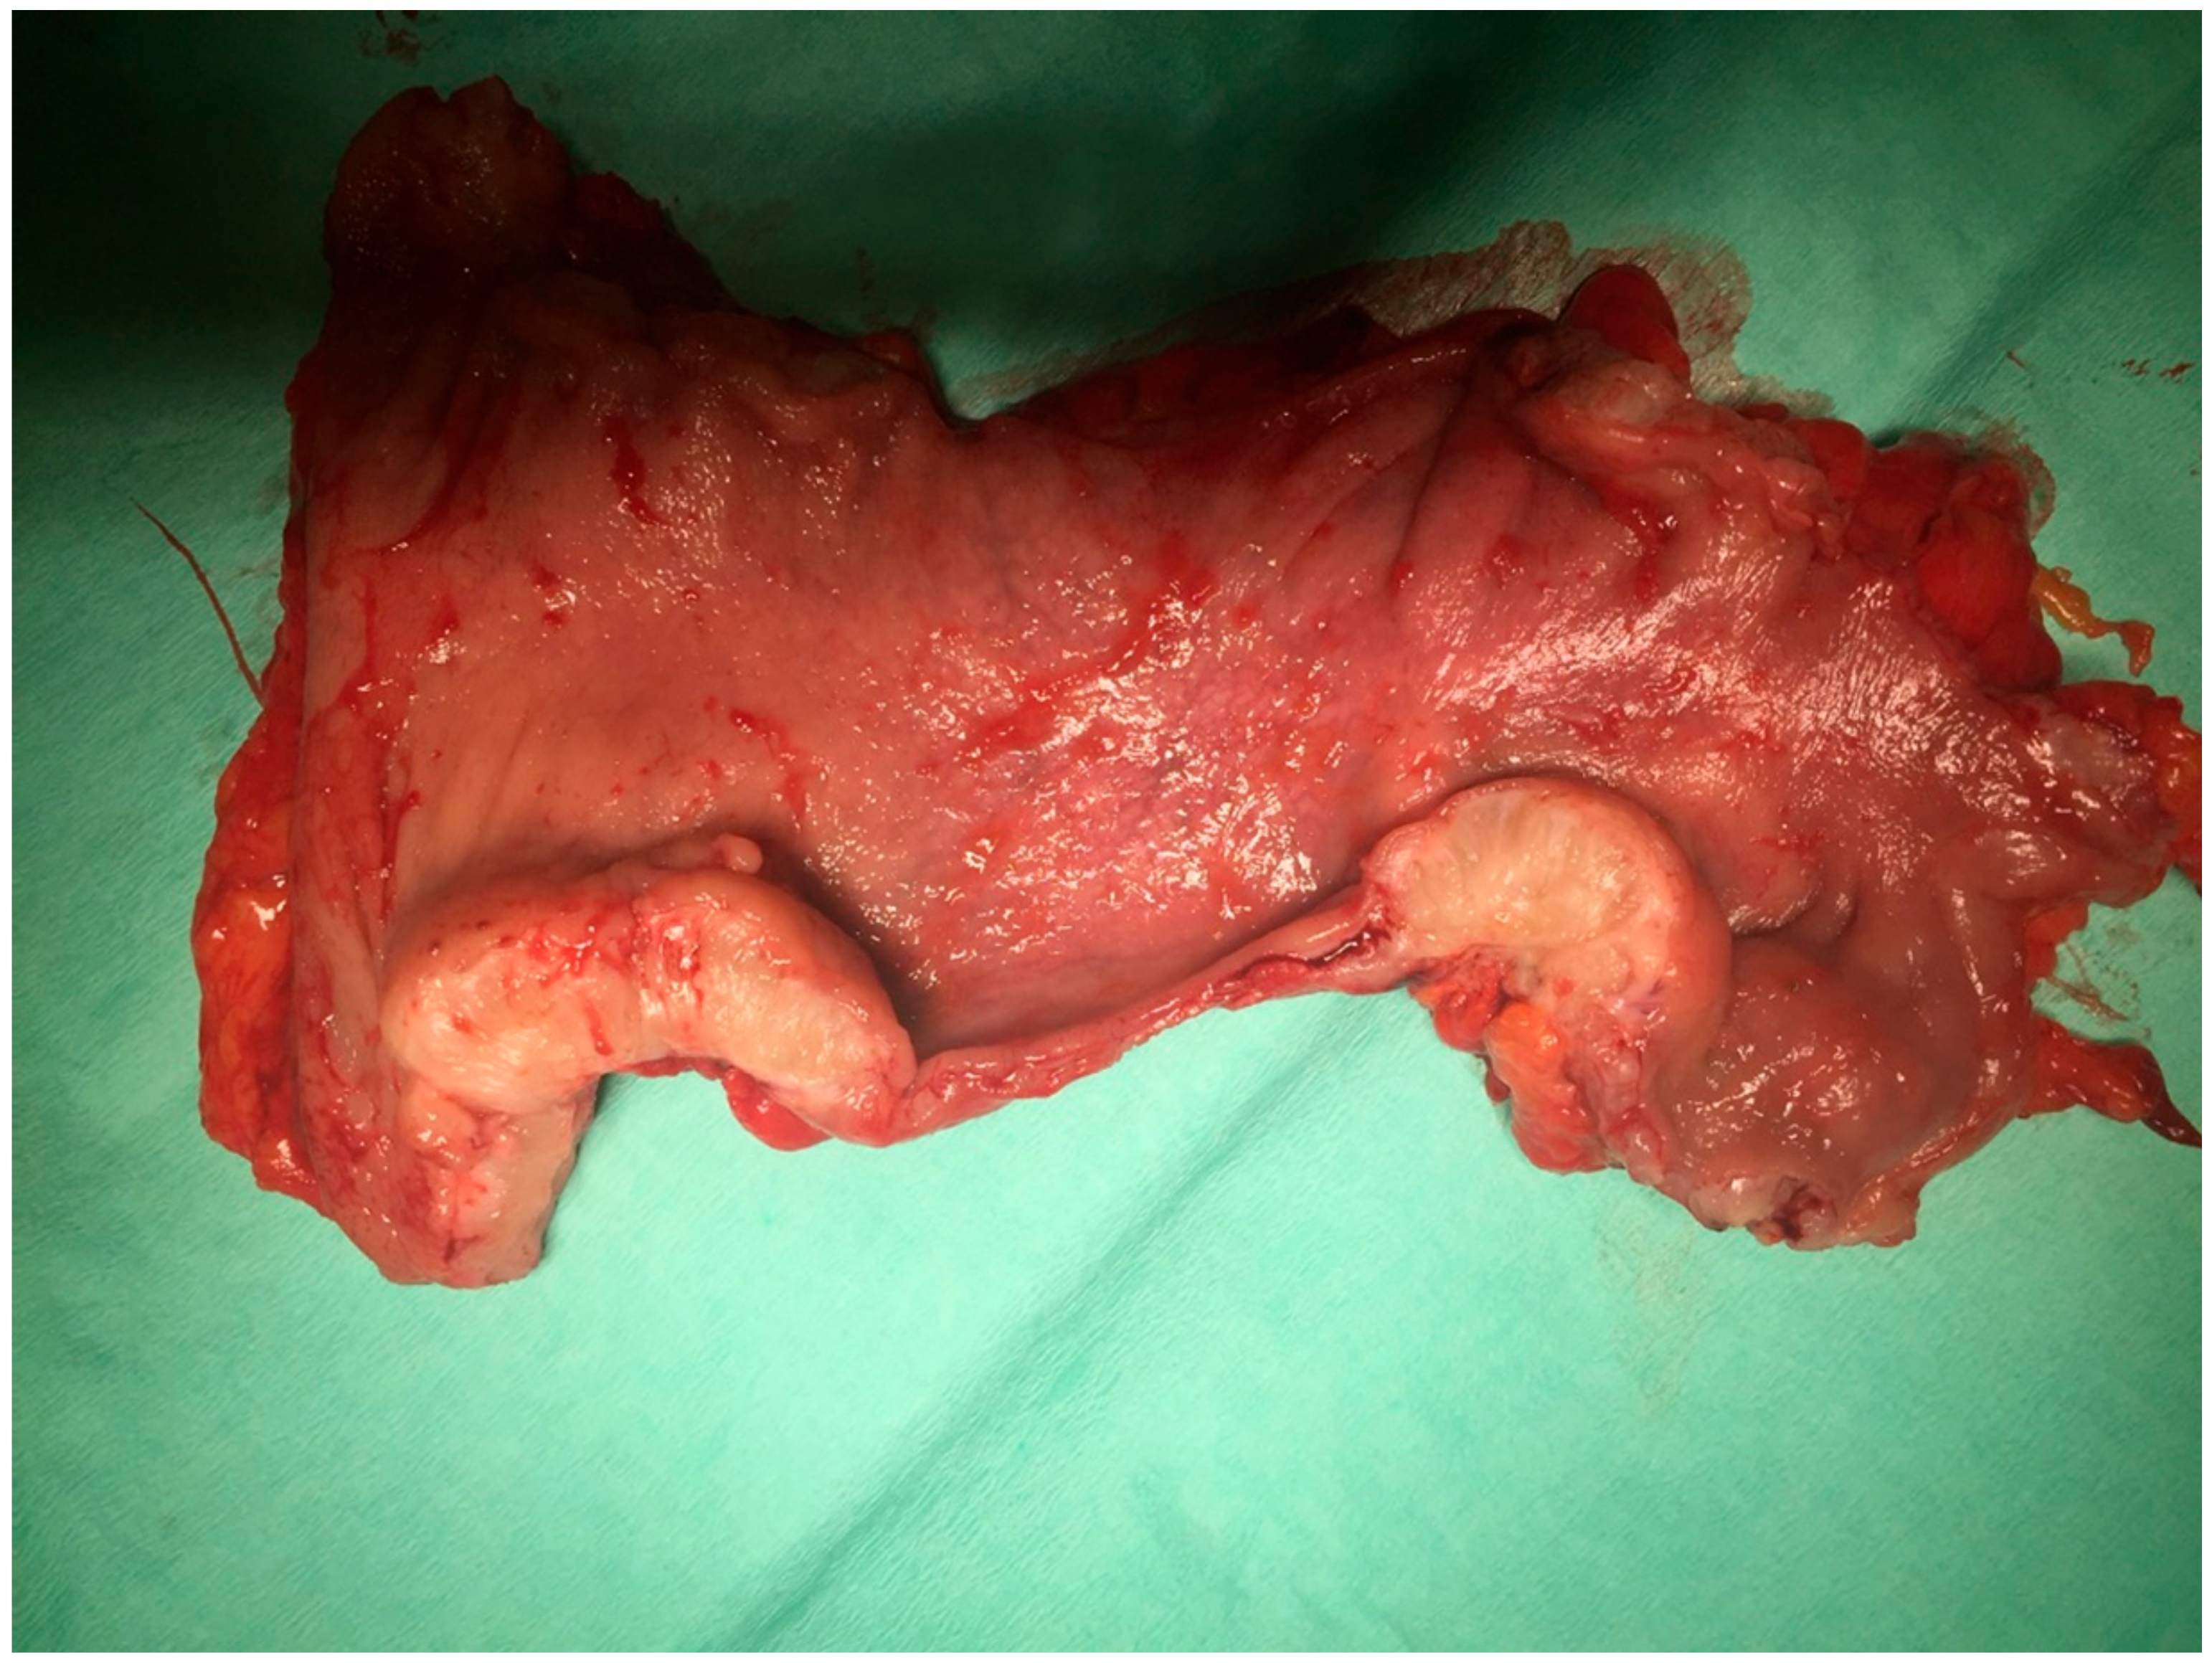

9.2. Surgical Treatment

- endometrial ovarian cysts.